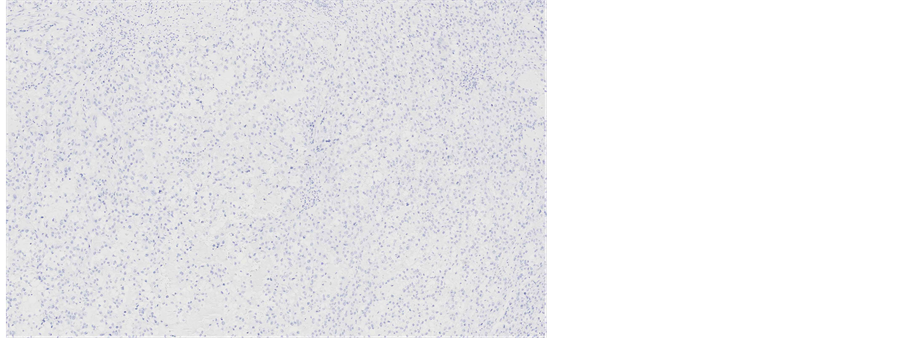

Immunohistochemical staining showed, that the tumour cells were diffusely positive for monoclonal antibodies against pancytokeratin (AE1/AE3) (Figure 5), cytokeratin 7 was positive in 5% of tumour cells (Figure 6), other markers, which showed immunoreactivity: EMA (5%), RCC-smp314 (30%), CA-125 (30%), p53 (was expressed weakly) (Figure 7), AMACR (diffuse positivity), CD10 (50%), Cyclin D1 (40% - 50%) and bcl-2. The tumour cells were negative for Vimentin (Figure 8), WT1 (Figure 9), Cytokeratin 20, ER/PR, CEA (Figure 10), TTF-1, CD57.

Figure 8. Microscopic appearance of the endometrial tissue from curetting specimen-clear cell carcinoma, immunohistochemical staining with monoclonal antibodies against Vimentin, ×10.